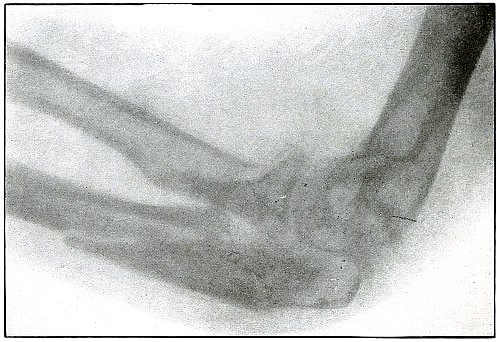

17. Gunshot fracture, elbow 44

18. Gunshot fracture, elbow 46

19. Gunshot fracture, elbow 48

20. Gunshot fracture, elbow 50

158. Gunshot fracture, ulna 326

159. Gunshot fracture, radius and ulna 328

160. Gunshot fracture, tibia and fibula 330

161. Amputation, knee 332

162. Excision, head of humerus 334 [Pg 7]